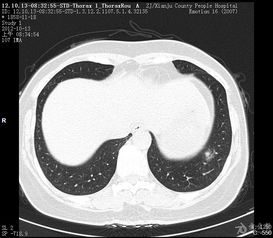

左肺下叶胸膜下的结节是从拍双肺的X光片,ct,甚至核磁共振等影像学的检查,所发现的一种病理性的描述,指的是在左肺下叶胸膜下的部位有占位性病变。

直径3mm左肺下叶的结节,是指在左肺下叶的某一个位置上长了一个肿块,一般为≤3cm的病灶。

这个病灶,有圆形的、椭圆形的,还有不规则形的,这种肿块性质无法确定,它主要是一种病变。

CT显示左肺下叶胸膜下小结节,小结节是肺癌前兆么?您好!根据您的具体详细描述,您检查结果提示左下肺胸膜下小结节。

这种情况,多见于结核、炎症、癌症等。